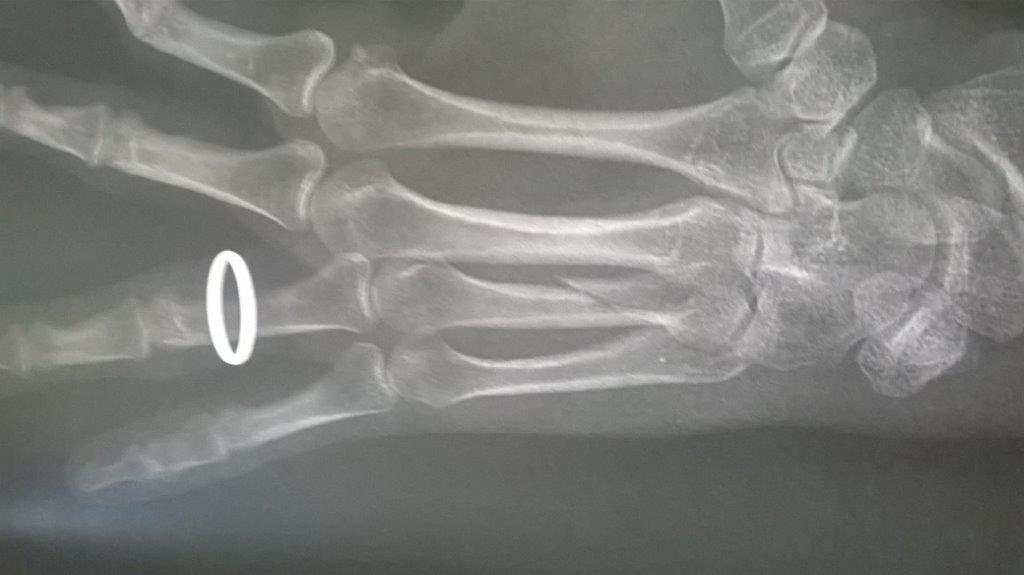

Résultat : fracture de la main gauche

Fichier(s) joint(s):

WP_20170914_001.jpg [ 47.5 Kio | Vu 29202 fois ]

Mais je confirme que ma saison de triathlon s'achève aujourd'hui. Main gauche immobilisé. Je suis au regret de déclarer forfait pour Paladru et d'abandonner les Mixirilliettes à leur triste sort